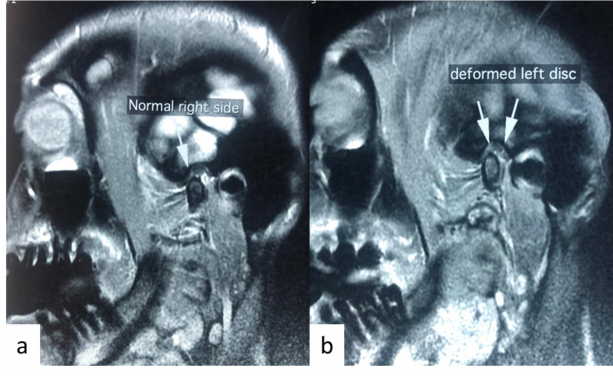

A patient with asymptomatic right TMJ and painful left TMJ with clicking upon opening. Magnetic resonance image shows a) normal TMJ and b) deformed articular disc at left TMJ.

The temporomandibular joints (TMJ) are located in front of the ears. If you use your fingers to lightly press the recess in that place and open and close your mouth, you will feel the temporomandibular joint move. Muscle pain and joint disorders are the common causes of temporomandibular joint and muscle disorder (TMD). In the case of muscle pain, it may be related to parafunctions such as gum chewing, eating hard foods, clenching and tooth grinding at night. For joint disorders, it may be related to disc displacement and inflammation. There is a cartilaginous disc between the jaw bone and temporal bone of the TMJ. If the disc becomes displaced, one may experience clicking or popping sounds during jaw function, and may contribute to pain in the TMJ or limited mouth opening. The pain may also spread to the head, face, or teeth etc.